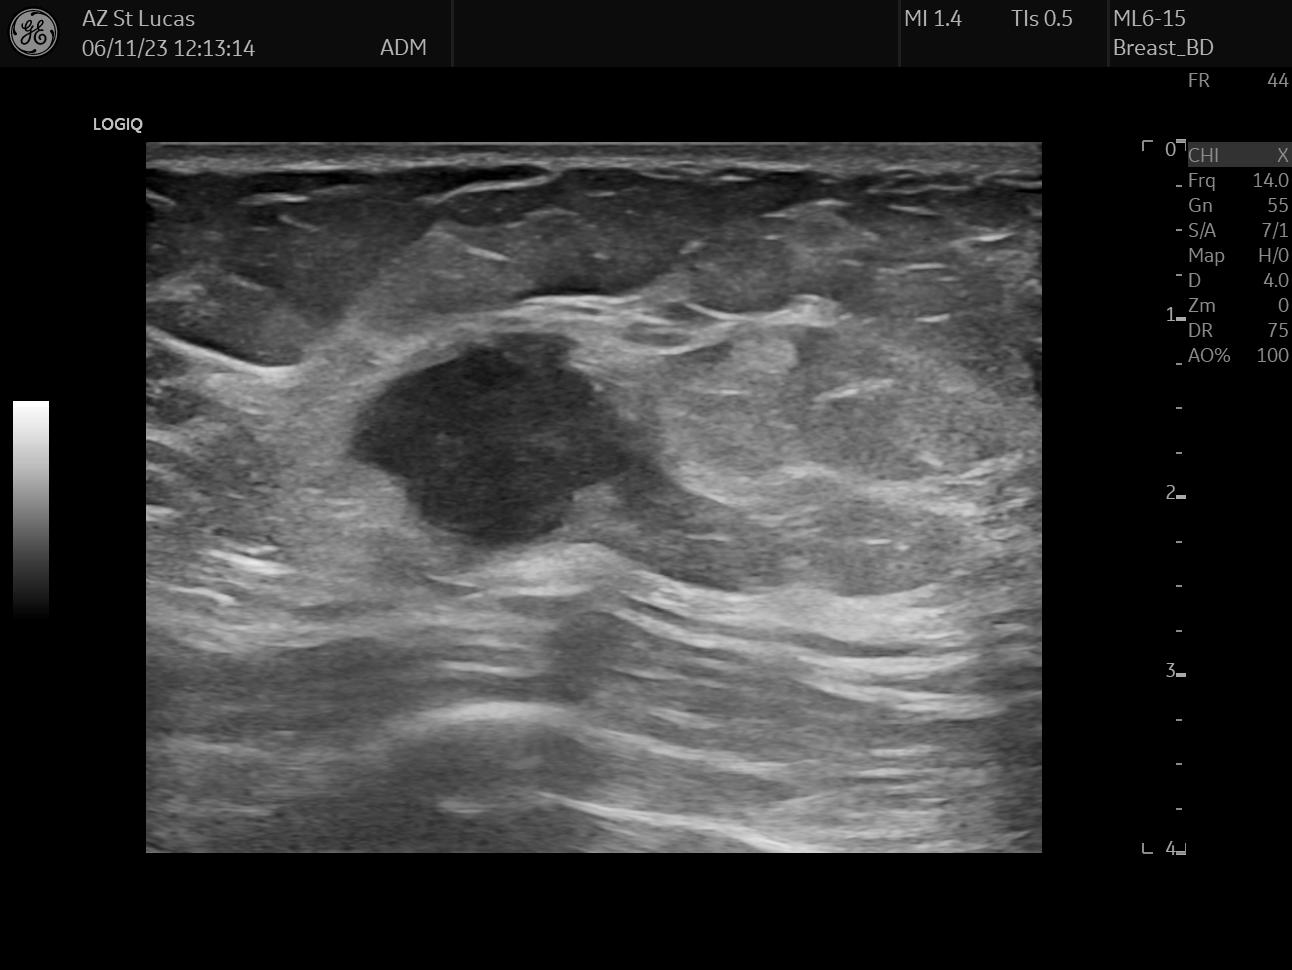

At this point of the ordeal we still needed to take care of two things, and both of these had to do with implanting stuff in my body. The first thing we inserted was a little clip in my breast, a tiny titanium marker used to pinpoint the exact position of the tumor. If we were going, hopefully, to kill the whole tumor, the clip was going to guide the surgeon find the correct area for removal later on. Furthermore, the clip was going to be monitored during imaging exams in the course of chemotherapy to understand changes over time.

This procedure happens with the same principle of a biopsy: a needle is inserted in the breast, but instead of taking tissue material away, the needle leaves the small clip behind. In the records I have selected from this procedure you can see the lesion in my breast, the long needle inside it, and eventually the clip in the middle of the tumor.